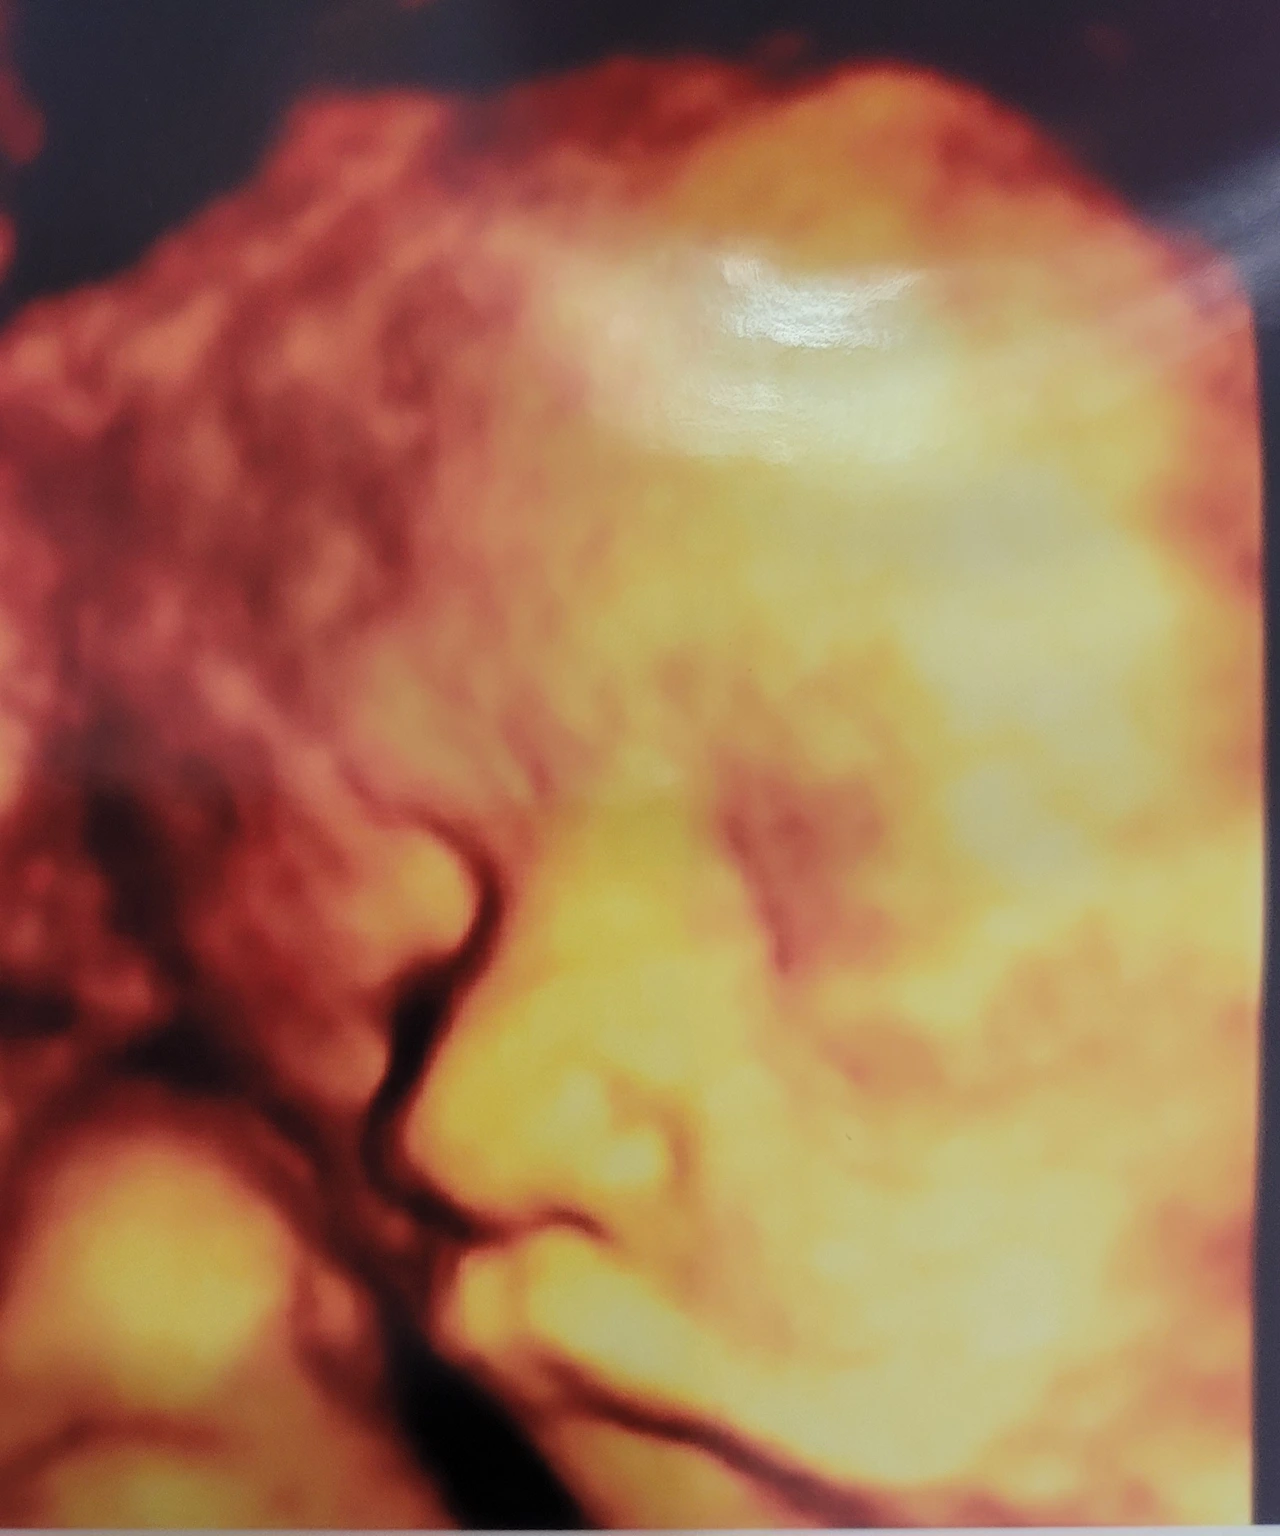

호두 만나기 전 D-90

출산을 앞두고

호두야, 안녕. 네가 이 글을 언제쯤 보게 되려나. 궁금하구나. 오늘은 임신 27주 차가 되었어. 임신 후 20주 차부터 왼쪽 손목이 도무지 나아지질 않고 하루하루 더 아파서 걱정이야.

이제 호두를 만날 날이 백일도 채 남지 않았어. 여러 가지 감정이 드는 시점이야. 엄마는 호두가 나오면 바로 오랜 시간 함께 하고 싶어서 조리원도 가지 않기로 했어. 24시간 호두와 함께하면서 호두가 원할 때는 언제든 함께하려 해. 출산휴가, 육아휴직도 최대한으로 써서 1년 3개월을 모두 쉬기로 했어. 아기가 태어나서 3년까지가 가장 중요한 시기라고 해. 그때 호두 곁에 엄마가 항상 있고 싶어서 그런 결정을 내렸어.